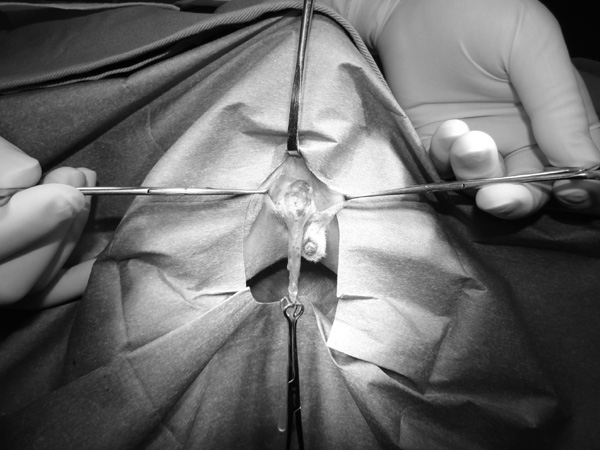

5~6歳以上の去勢手術をしていないオス犬に多い病気ですが、メス犬や去勢した犬に起こることもあります。お尻の筋肉が萎縮した結果、筋肉の隙間から直腸や膀胱が皮膚の下にとびでてしまいます。これにより便が出にくくなったり膀胱炎になったりします。手術をすることで機能回復および今後の致死的な状況を回避することができます。当院では去勢手術→結腸固定→前立腺固定→骨盤隔膜構成筋の縫縮→内閉鎖筋フラップ→浅臀筋フラップの順で通常腹側・臀部左右両側同時に行います。また老化以外に、筋肉が萎縮する原因があったり、腹圧がかかる原因があったりする場合も多いので、再発防止のためそれらの診断・治療も重要です。今回のワンちゃんも無事手術も終わり元気に退院しました。よかったね。